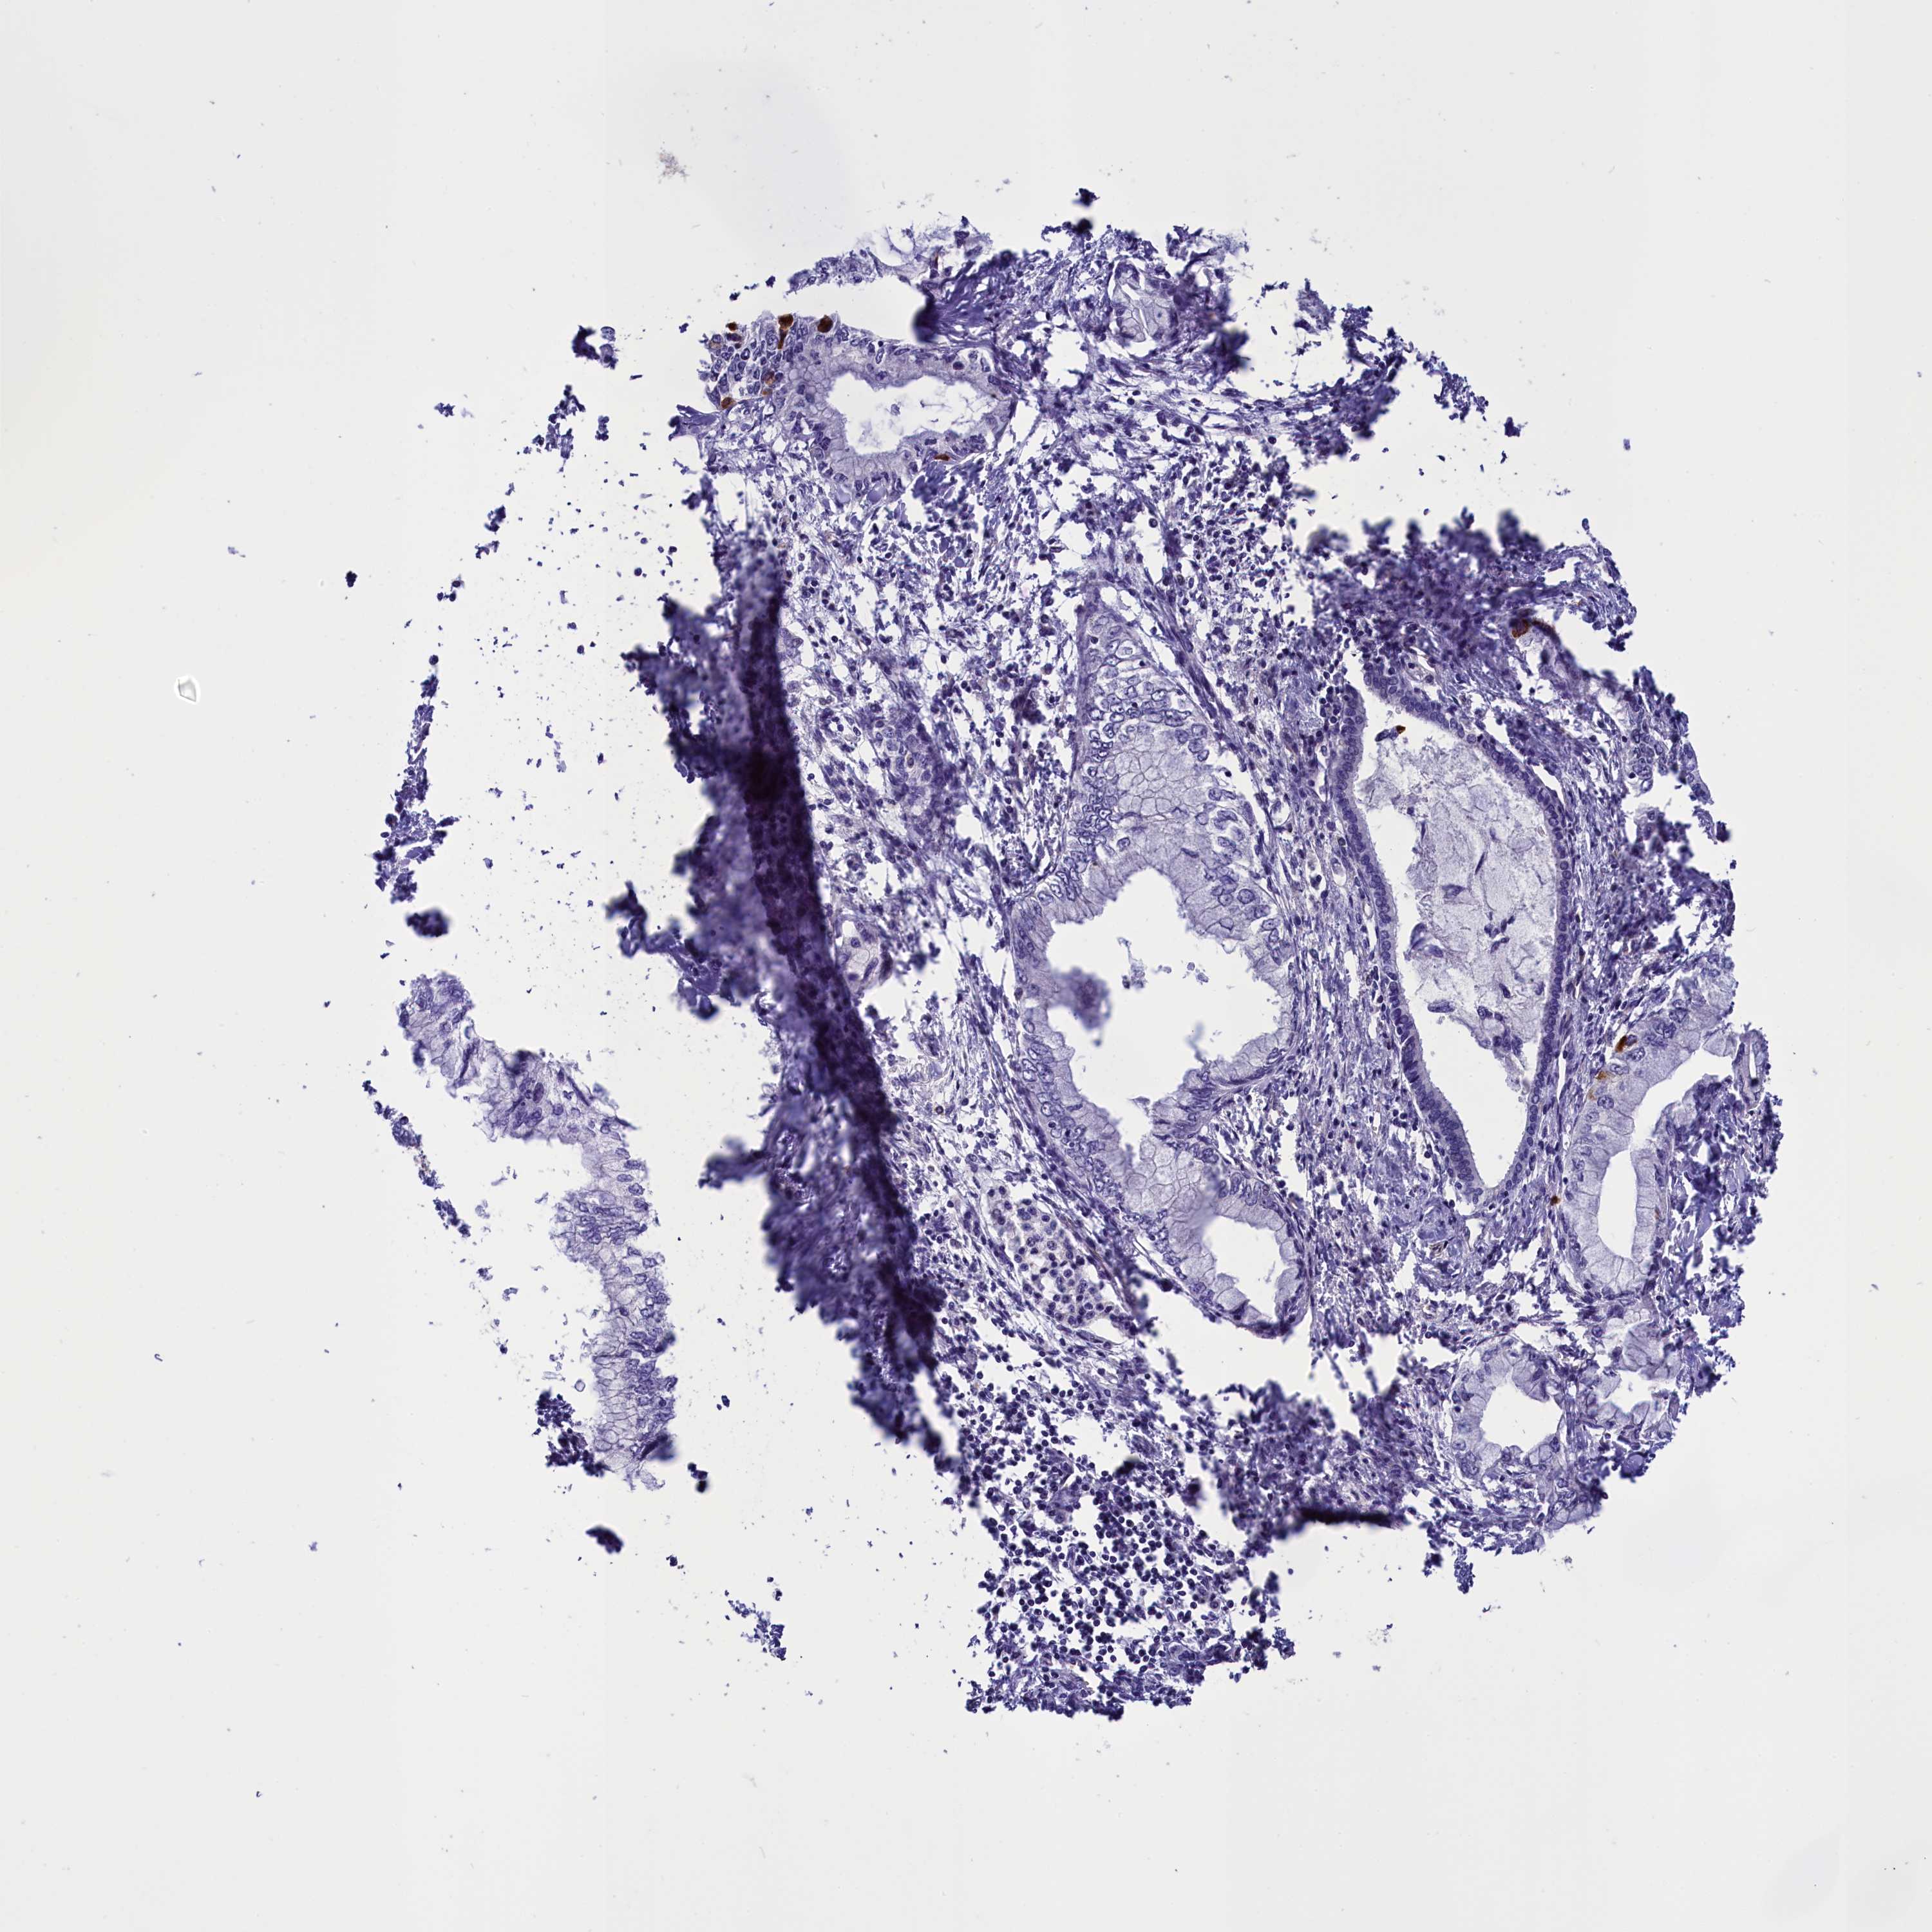

PANCREATIC CANCER - Protein expressioni

A mouse-over function shows sample information and annotation data. Click on an image to view it in a full screen mode. Samples can be filtered based on level of antibody staining by selecting one or several of the following categories: high, medium, low and not detected. The assay and annotation is described here.

Note that samples used for immunohistochemistry by the Human Protein Atlas do not correspond to samples in the TCGA dataset.

Antibody stainingi

Antibody staining in the annotated cell types in the current human tissue is reported as not detected, low, medium, or high, based on conventional immunohistochemistry profiling in selected tissues. This score is based on the combination of the staining intensity and fraction of stained cells.

Each image is clickable and will lead to virtual microscopy that enables deeper exploration of all samples and also displays staining intensity scores, fraction scores and subcellular localization as well as patient and tissue information for each sample.

Antibody HPA041913

Staining

High

Medium

Low

Not detected

Intensity

Strong

Moderate

Weak

Negative

Quantity

>75%

75%-25%

<25%

None

Location

Nuclear

Cytoplasmic/membranous

Cytoplasmic/membranous,nuclear

Adenocarcinoma, NOS